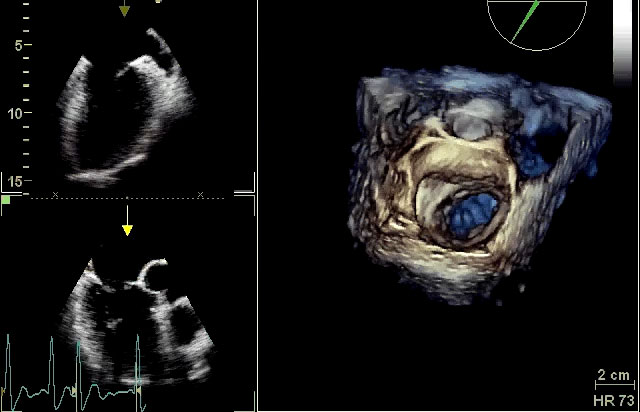

Valvola mitralica

Autore:

Daniela Torta

Valvola aortica e mitralica

Manuela Muratori